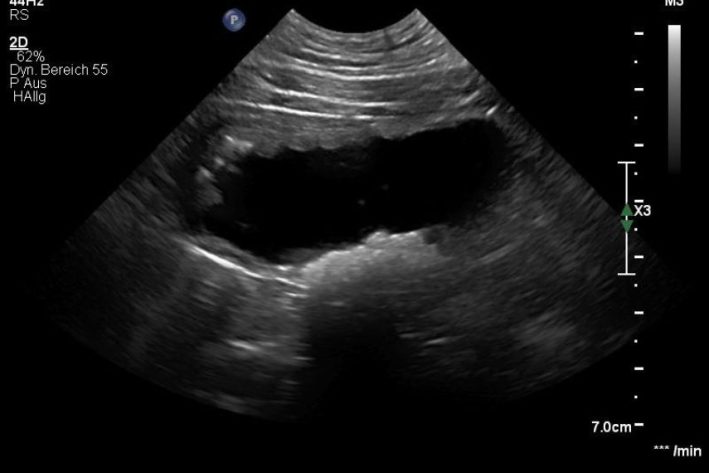

Bildgebende Diagnostik: Mittels Röntgen können röntgendichte Harnsteine sichtbar gemacht werden. Eine Ultraschalluntersuchung ermöglicht eine detaillierte Aussage zur Schleimhautbeschaffenheit und dem Harnblaseninhalt. Weiters kann ultraschallgestützt eine sterile Punktion des Harns vorgenommen werden.

Zystitis Ultraschall